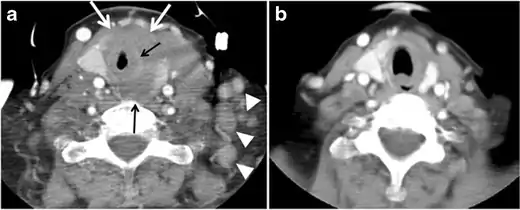

Fig. 11. Thyroid non-Hodgkin's large B-cell lymphoma in a 66-year-old female patient. an Axial enhanced neck CT scan demonstrates left thyroid lobe and isthmus homogeneously hypodense and minimally enhancing mass (white arrows). This lesion invades the prevertebral muscles (black arrows). Note the multiple enlarged level V lymph nodes (white arrowheads). b Post-treatment image shows significant reduction in size and mass effect of the left thyroid infiltrative mass, with almost complete resolution of the left cervical lymphadenopathy.[1]